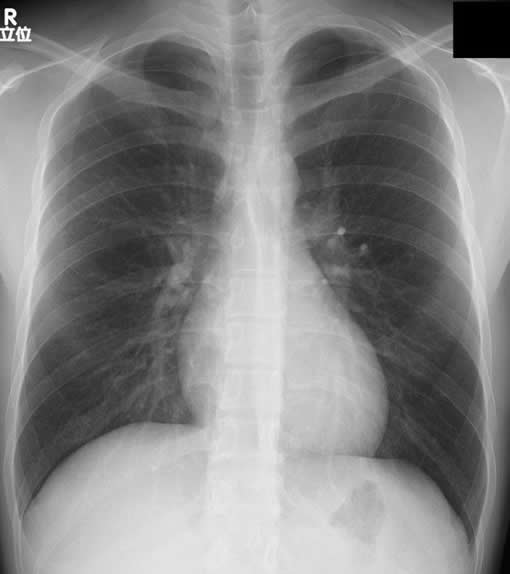

一般X線撮影

胸部、腹部、全身の骨・関節の撮影を行っています。当院では、FPD(フラットパネルディテクタ)システムにより、画像はデジタル化されており、被ばく低減や画質の安定性を実現しています。

胸部